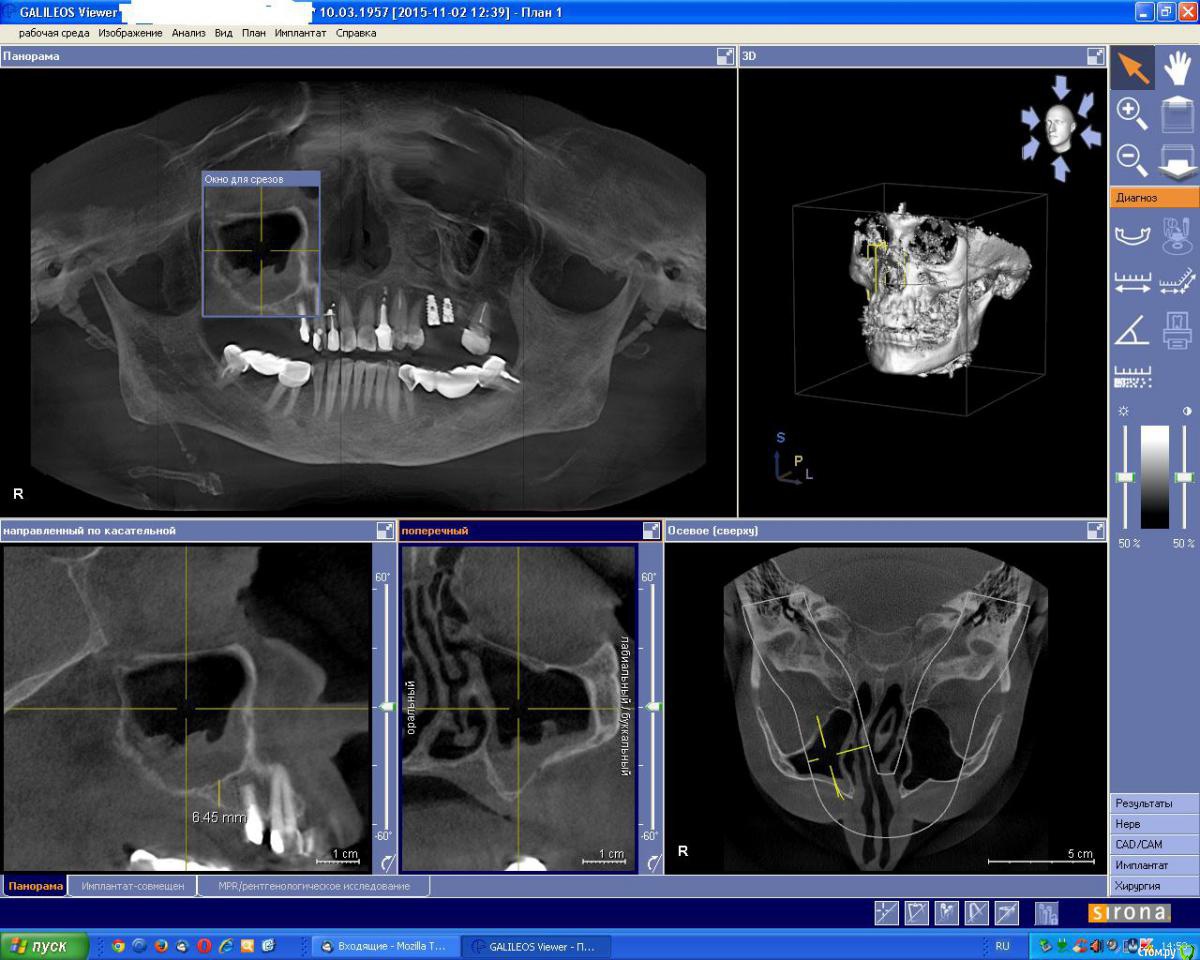

an_ver Опубликовано 2 ноября, 2015 Поделиться Опубликовано 2 ноября, 2015 Вот такое КТ..думаю делать нельзя.Ваше мнение коллеги? Ссылка на комментарий

an_ver Опубликовано 2 ноября, 2015 Автор Поделиться Опубликовано 2 ноября, 2015 (изменено) Соустье закрыто..или еле открыто...и чет гипертрофия слизистой не нравиться.А сосудик в стенке светит)) Изменено 2 ноября, 2015 пользователем an_ver Ссылка на комментарий

Abuk Опубликовано 3 ноября, 2015 Поделиться Опубликовано 3 ноября, 2015 (изменено) Вот такое КТ..думаю делать нельзя.Ваше мнение коллеги?Согласен с Олегом. Планировали 1 имплантат ? Может гребень попробовать восстановить. Одномоментно я не рискнул бы. Далее повторно кт и закрытый синус или открытый) Изменено 3 ноября, 2015 пользователем Abuk Ссылка на комментарий

an_ver Опубликовано 3 ноября, 2015 Автор Поделиться Опубликовано 3 ноября, 2015 Согласен с Олегом. Планировали 1 имплантат ? Может гребень попробовать восстановить. Одномоментно я не рискнул бы. Далее повторно кт и закрытый синус или открытый)14 уходит.Планировал открытый сделать.Импланты в позиции 14,15,16 Ссылка на комментарий

gum Опубликовано 5 ноября, 2015 Поделиться Опубликовано 5 ноября, 2015 Можно уточнить почему на открытый синус не решаетесь, если хотите сделать закрытый. Риски мне кажется примерно одинаковы. Сосуд светит, но окно можно пониже или я ошибаюсь? 1 Ссылка на комментарий

an_ver Опубликовано 5 ноября, 2015 Автор Поделиться Опубликовано 5 ноября, 2015 Можно уточнить почему на открытый синус не решаетесь, если хотите сделать закрытый. Риски мне кажется примерно одинаковы. Сосуд светит, но окно можно пониже или я ошибаюсь?Я и не собирался закрытым)) почему так решили? Сосуд мелкого диаметра не проблема.Сегодня сделаю.Получится,отфотаю Ссылка на комментарий